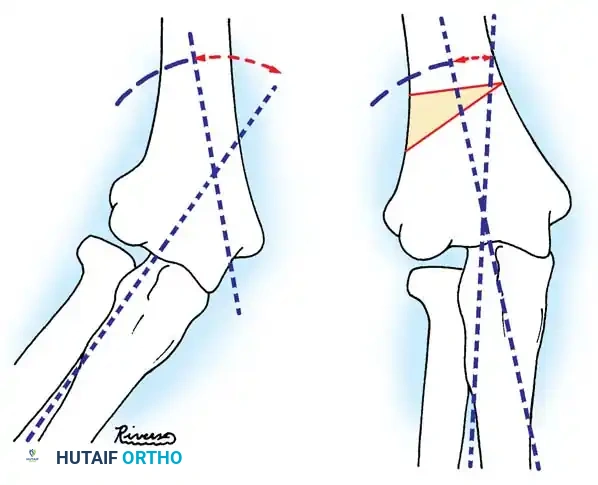

In cases of chronic radial head dislocation (often missed acutely or associated with plastic deformation of the ulna), simple open reduction is insufficient. The Hirayama Technique utilizes an ulnar osteotomy to overcorrect the angular deformity, thereby pulling the radial head back into the joint via the interosseous membrane.

TECHNIQUE 33-5: Osteotomy of the Ulna (Hirayama et al.)

- Preparation: Inflate a pneumatic tourniquet. Make a posterolateral skin incision exposing the radiohumeral joint and proximal third of the ulna. Excise intra-articular scar tissue.

- Osteotomy: Perform a subperiosteal osteotomy of the ulna 5 cm distal to the olecranon.

- Distraction and Angulation: Distract the osteotomy by 1 cm to lengthen the ulna.

- For Anterior Dislocation: Correct by posterior angulation of the ulna.

- For Lateral Dislocation: Correct by medial angulation of the ulna.

- Fixation: Secure the osteotomy with a metal plate bent to approximately 15 degrees. Ensure the radial head rests perfectly within the radial notch of the ulna without excessive radiocapitellar pressure.

Fig. 33-36 Overcorrection with posterior convexity for anterior dislocation.

Fig. 33-37 Overcorrection with medial convexity for lateral dislocation.